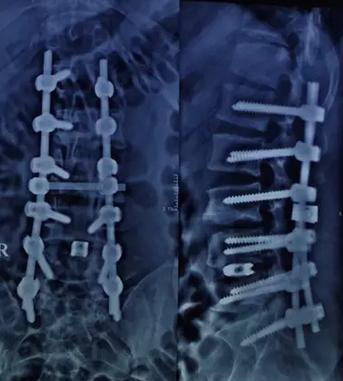

术后照片

征询小张及其亲属意见后,由中山骨科医院胡院长主刀,为小张行L4/5,L5/S1椎间盘摘除、椎间植骨融合,L1-S1矫形、钉棒内固定术。由于患者病情严重,手术有一定的难度与风险,但是凭借着胡院长40几年的经验以及所有医务人员的信心,手术进行的有条不紊,终顺利结束。